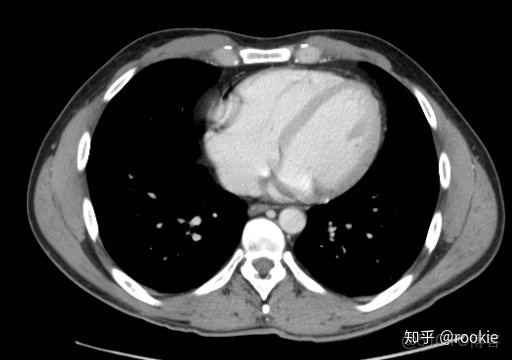

CTA窗口窗口設置: (W:600,L:170)或(W:650,L:225)優點: 在評估CT血管造影研究(或在血管中具有明顯對比的CT掃描的任何階段)時,此設置可用於嘗試清晰地觀察血管病變。它在提供目標血管信號的同時具有良好的平衡,而無需血管內的亮度過高會沖洗腔內病變。

CLAHE算法增強局部對比度的X光圖像增強效果對比_ico_14

此窗口用於在感興趣的血管中有相當大的對比度的情況下(例如CT血管造影)。